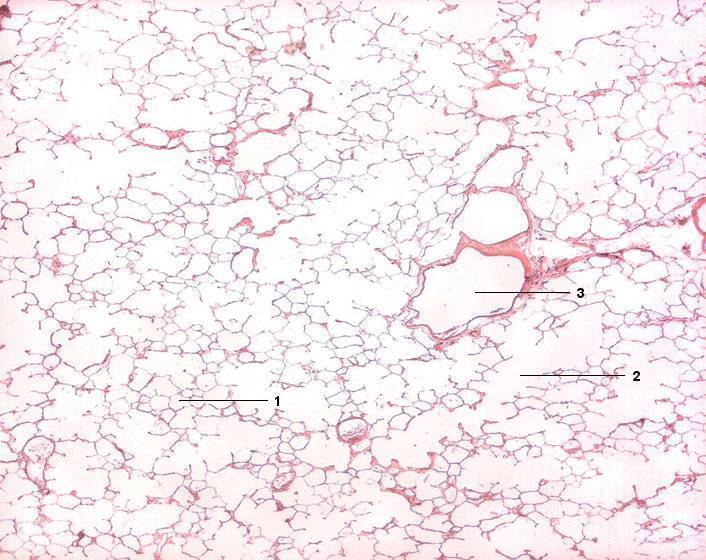

1 Alveolen

2 Ductus alveolaris

3 Bronchiolus